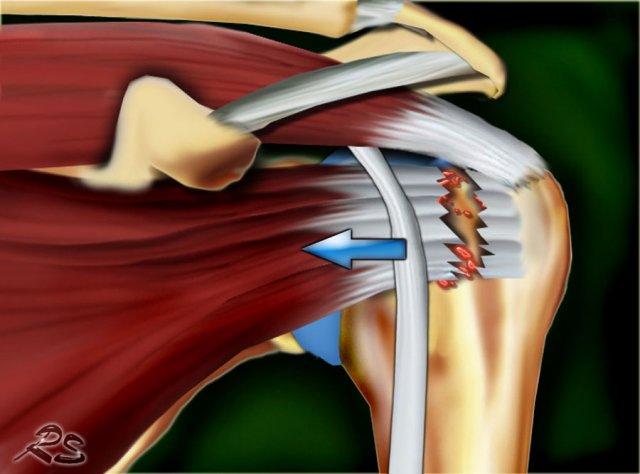

- Trật khớp ngoài khớp (hình minh họa)

Trật đầu dài gân cơ nhị đầu

Tổn thương dây chằng ngang xương cánh tay có thể dẫn đến trật gân cơ nhị đầu về phía trong.

Gân cơ nhị đầu có thể di chuyển vào trong hoặc bên dưới gân cơ dưới vai khi gân cơ dưới vai bị đứt.